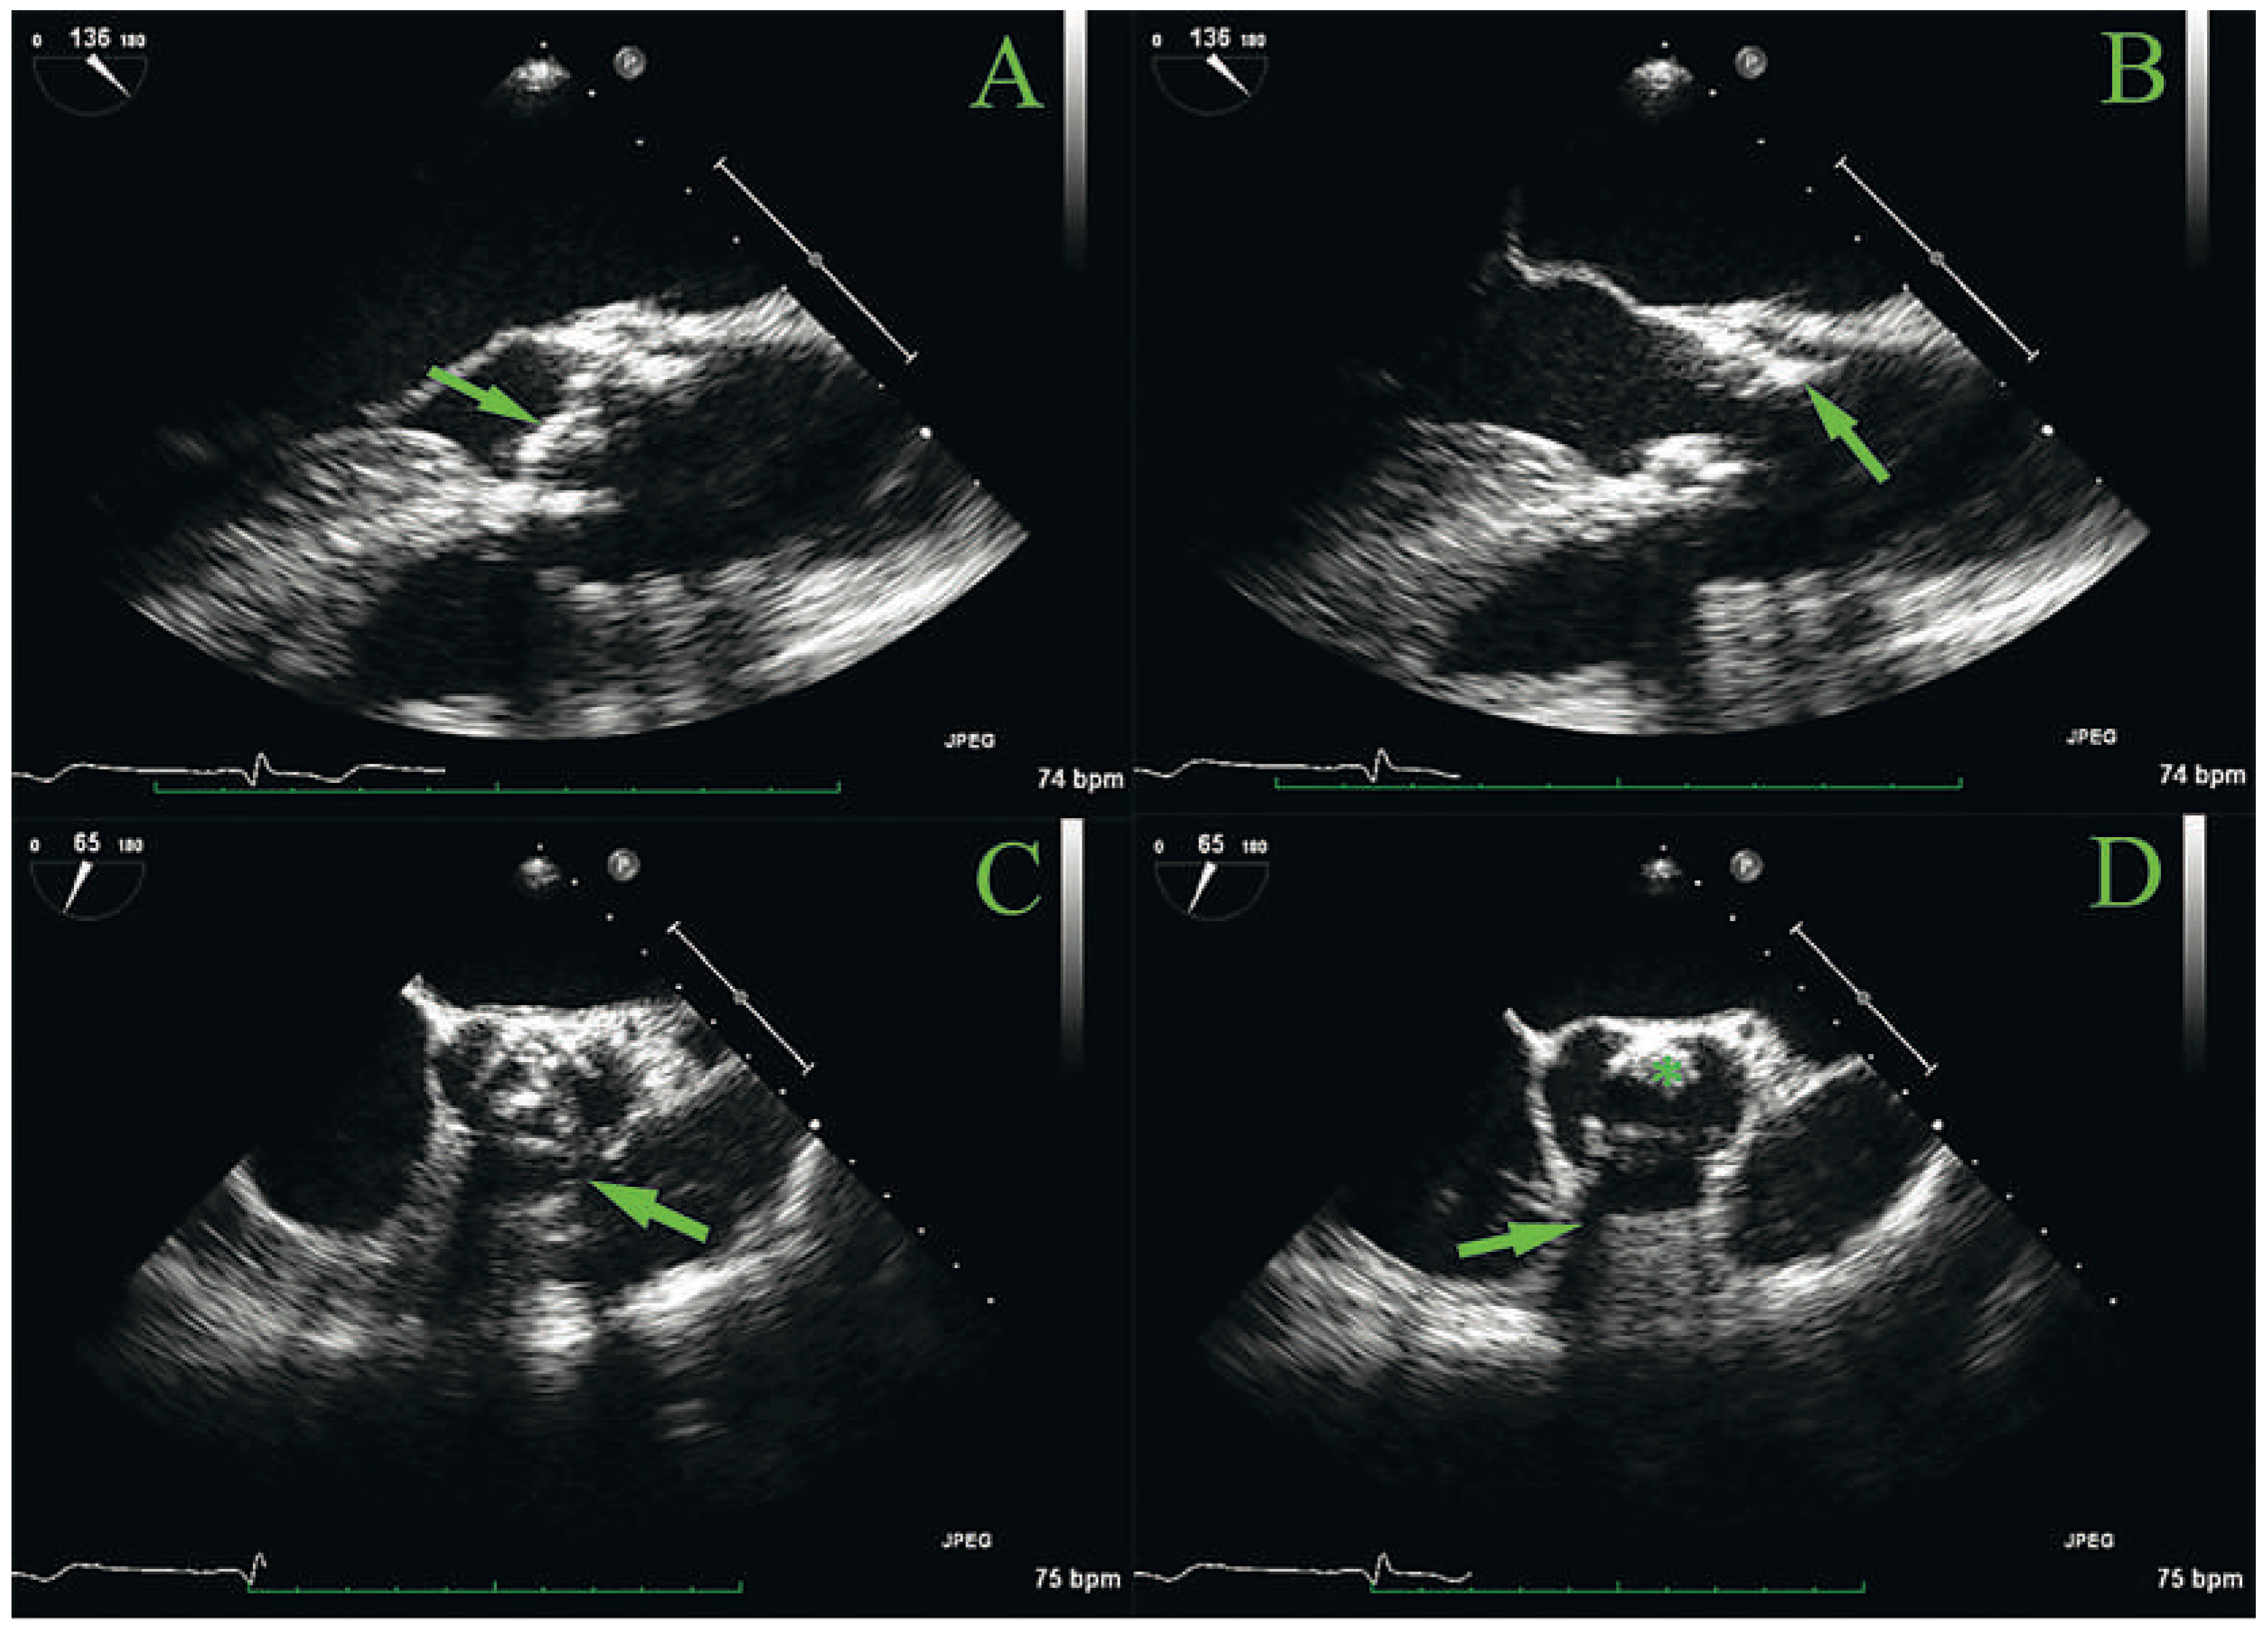

Eight years later, the patient, now aged 54, consulted because of the recent appearance of dyspnoea on exertion after 3–4 flights of stairs. Auscultation revealed a 3/6 aortic murmur, and transthoracic echocardiography showed a normal-looking bioprosthesis but with accelerated peak jet velocity (3.8 m/s), a mean gradient of 35 mm Hg and a calculated effective orifice area (EOA) of 1.3 cm2 (0.65 cm2/m2). LVEF was still normal at 70%. Six months later, the aortic jet velocity had increased to 4.6 m/s with a mean transvalvular gradient of 50 mm Hg and the EOA was 1.1 cm2 (0.55 cm2/m2). Transoesophageal echocardiography (Figure 1) showed mild thickening of the cusps, which could not clearly explain the dysfunction of the prosthesis. There was a suspicion of a superimposed mass located adjacent to the struts in the posterior position (Figure 1, panel B), but visualisation of the cusps was slightly hampered by shadowing and reverberation of the struts. Colour Doppler showed mild prosthetic regurgitation. Because the presentation was not typical of valvular prosthesis degeneration, it was decided to start the patient on empirical oral anticoagulation with acenocoumarol to treat putative obstructing thrombus.

Figure 1. Transoesophageal echocardiography of the aortic bioprosthesis. A and B: long axis view with cusps in the closed (panel A, arrow) and open (panel B) position; the arrow in panel B points to a possible superimposed mass adjacent to the struts in the posterior position. C and D: short-axis view, also with cusps in the closed (Panel C) and open (panel D) position. Note examples of shadowing of the struts (panels C and D, arrows). The asterisk represents a possible superimposed mass adjacent to the struts in the posterior position.